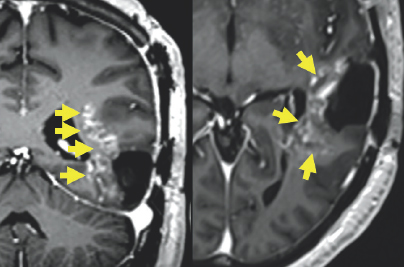

(Left) Gray colored variations are enclosed by black and white outlines. To the right of the center of the image, there is a white blob with gray variations highlighted by four yellow arrows on the left side of the blob. (Right) Gray variations are enclosed by black and white outlines. There is a white blob with variations of gray surrounding it on the right side of the image. This blob is highlighted by three yellow arrows.

FIGURE 2.4 Brain MRI after surgery. Imaging shows post-treatment and post-operative changes from resection of the left temporal tumor. There are patchy and irregular areas of abnormal enhancement within the medial margin of the surgical cavity that appear bright after being injected with IV contrast (yellow arrows), uncertain for residual tumor versus post-treatment changes.

(Left) A variation of gray colored structures are surrounded by a black and white outline. On the top right of the image, there is a small white blob highlighted by a yellow circle. (Right) A variation of gray colored structures are surrounded by a large black and white outline. There is a small white blob in the center of the image highlighted by a red circle. There are two additional gray blobs with white coloration on them highlighted by two yellow arrows on the right side of the image.

FIGURE 2.5 Brain MRI after surgery. Imaging shows post-treatment and post-operative changes from resection of the left temporal tumor. There is interval decreased abnormal patchy enhancement within the medial left temporal lobe (yellow circle) and stable tiny enhancing lesion within the left aspect of the midbrain (red circle), which are also uncertain for residual tumor versus post-treatment changes.